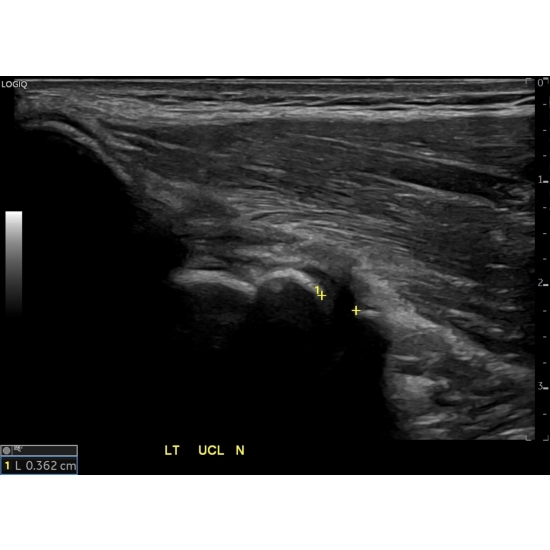

Ultrasound Elbow: Tear of the anterior band of the left ulnar collateral ligament with abnormal laxity on valgus stress. The joint space gaps an average of 2.5 mm with valgus stress. A representative portion of the dynamic ultrasound here showed an abnormal gapping of 2.76 mm between the trochlea and coronoid process when comparing the neutral position Case Photo #3 to the valgus stress position Case Photo #4 . There was no gapping on the contralateral side.